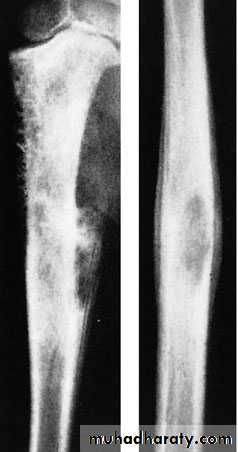

Malignant tumor of vascular endothelium of bone marrow.Occur at the diaphysis of long bones commonly tibia, fibula and clavicle.

It causes severe type of periosteal new bone formation.

X-ray shows diaphysial lesion with bone destruction and multiple layers of periosteal new bone formation.New bone formation may extend along the shaft and appears as fusiform layers of bone around the lesion – the socalled‘onion-peel’ effect or Onion-Skin appearance. is predominantly in the mid-diaphysis.

Often the tumour extends into the surrounding soft tissues, with radiating streaks of ossification and reactive periosteal bone, these features (the ‘sunray’ appearance and Codman’s triangles) are usually associated with osteosarcoma, but they are just as common in Ewing’s sarcoma.